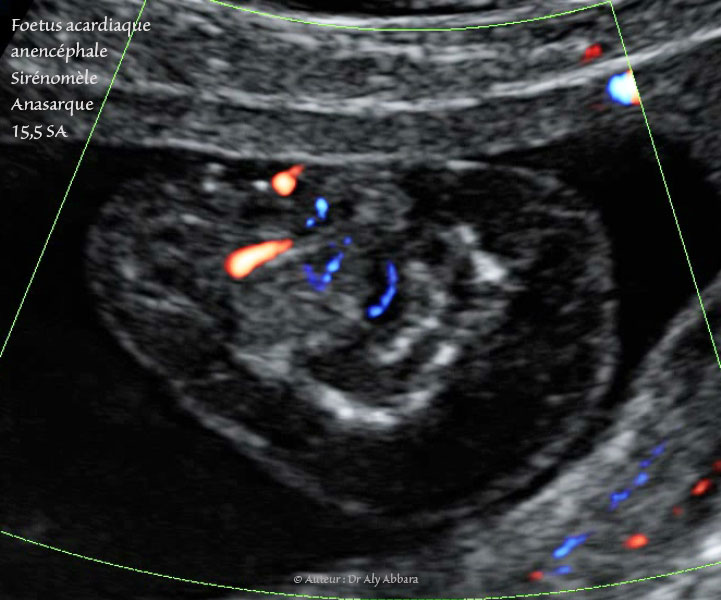

Grossesse gémellaire monochoriale bi-amniotique à 15,5 SA avec un jumeau polymalformé : vascularisation passive mise en évidence par (Doppler type Dynamic-Flow)

• Foetus acardiaque : pas structures cardiaques (holoacardius), mais la présence d'une vascularisation provenant de l'autre jumeau normal (jumeau pompe) par le cordon ombilical.

Anencéphale (acrânie - acranius) : absence de structures céphaliques identifiables.

• Sirénomélie : un seul membre inférieur comportant deux segments : supérieur avec un fémur, et inférieur contenant deux os longs, mais apodie (absence de pied). Ce membre inférieur est parfois animé par certains mouvements de type flexion - déflexion très réduites.

• Un œdème fœtale généralisé sous-cutané majeur enveloppant ce fœtus acardiaque.

L'estimation du poids de ce jumeau acardiaque est égale 7,7 grammes pour une longueur de 3,3 cm, contre 118 grammes + 10 % pour le jumeau pompe (donneur normal).